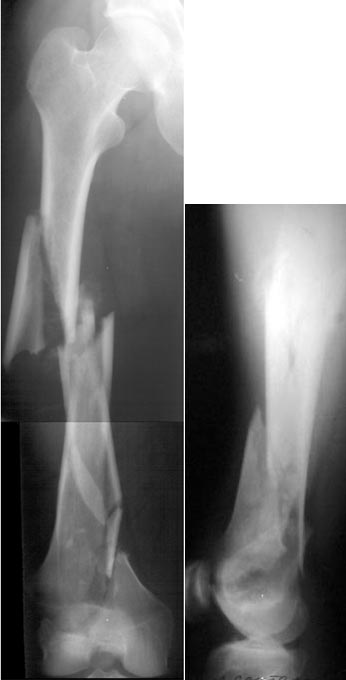

of course the only radiograms both the view of the femur (AP and LL) are not enough in order to assess the condilar ones.

If You're going to use a nail,it could be blocked proximally and distally,because of the spiroid rime of the fracture.

But,in my opinion,the real problem is the distal fracture and so I suggest the use of a long plate,long until the condilars

A CT and knee xrays would help identify lateral condyle comminution and/or a "hoffa fragment" of the posterior condyle. I am concerned that the lateral cortex is not sufficient to give purchase for a retrograde IMN. blocking screws could improve this as a possibility. A long blade or LISS if avaible would be my secondary choices. Good luck. Any chance you can get these cases transferred earlier when it

Lateral condyle looks too small for the blade, and the plate too short.